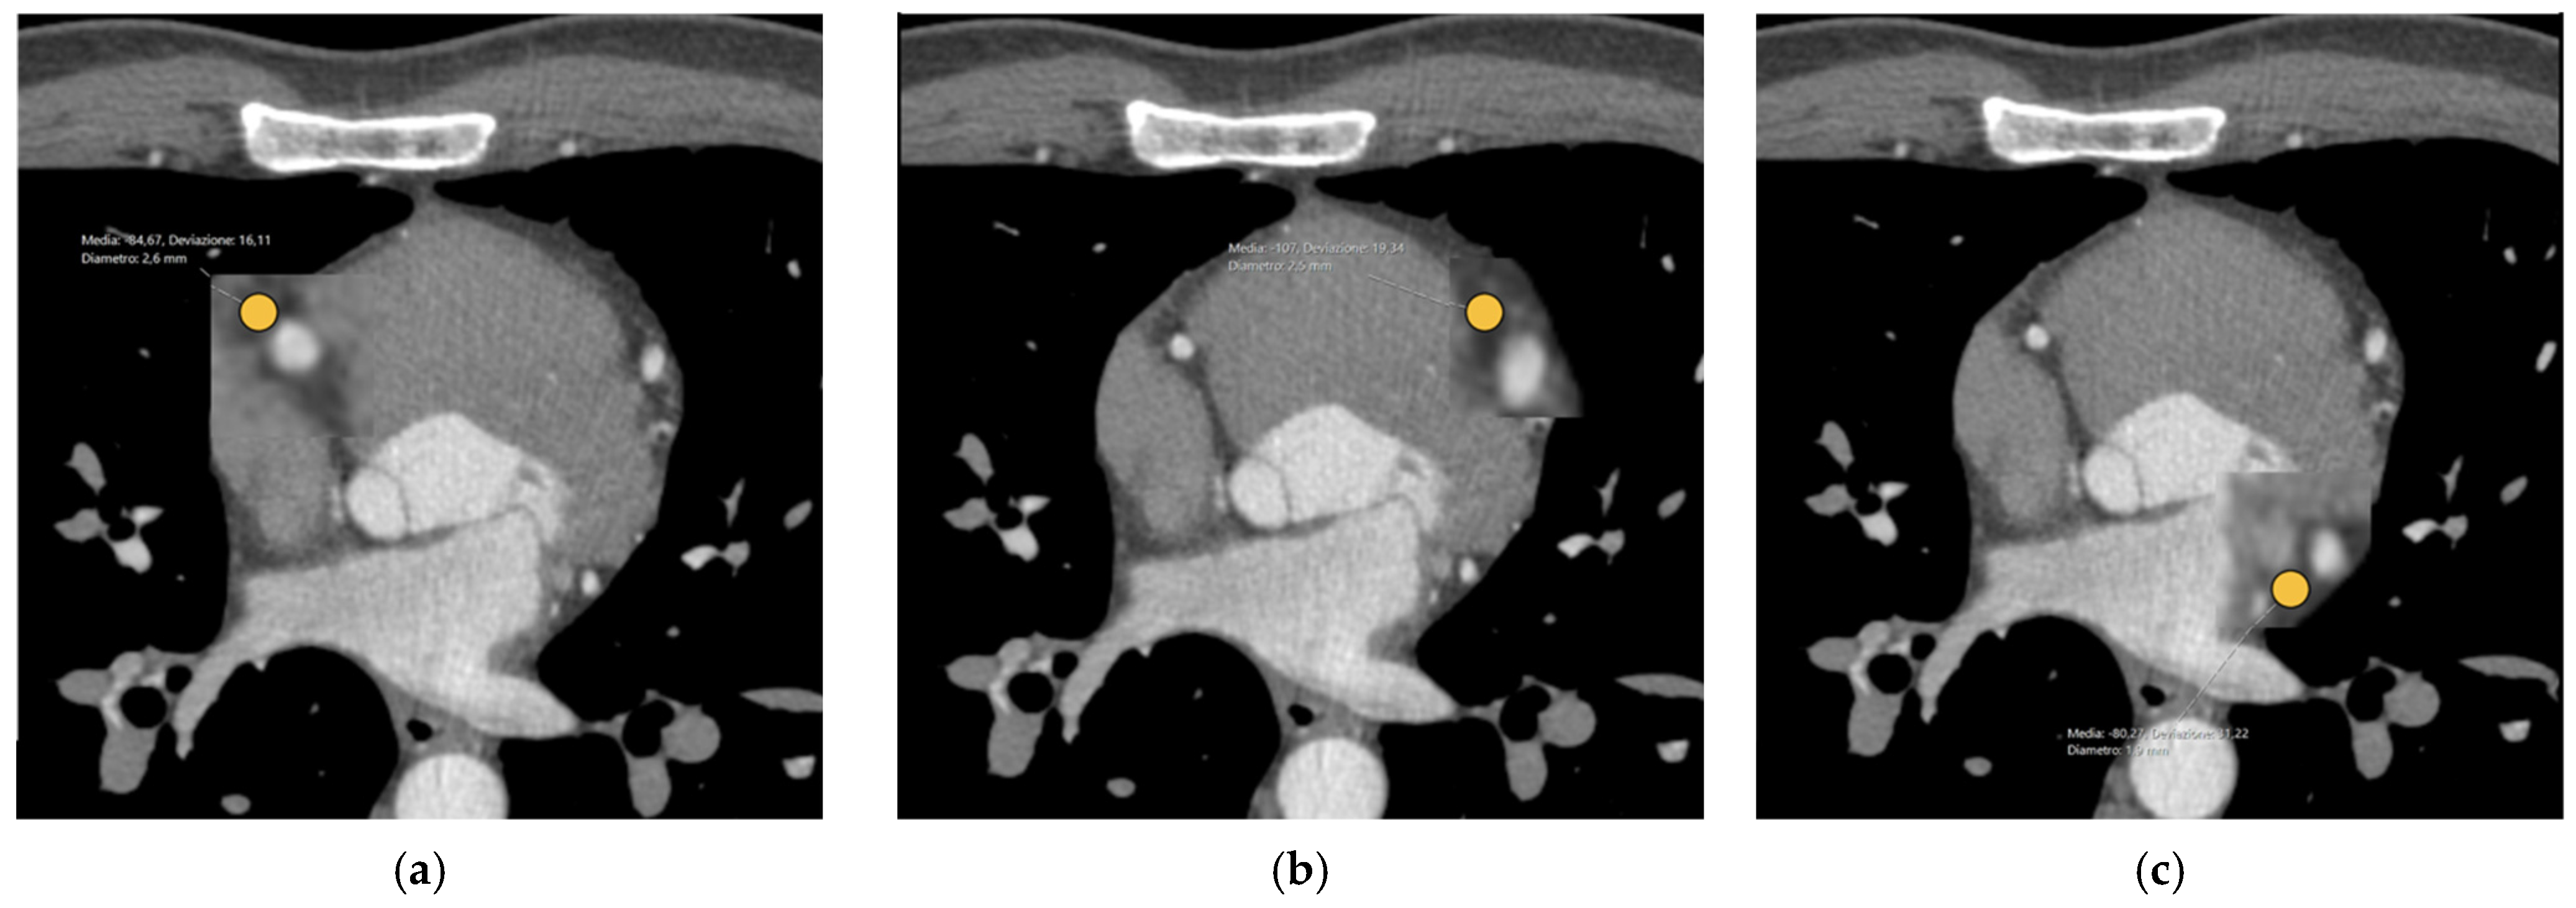

2.3. CCTA Image Evaluation